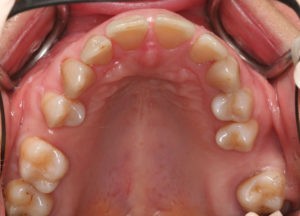

Пациентка, 43 года обратилась в клинику с жалобами на наличие промежутков между зубами, измененный наклон передних зубов верхней челюсти, появившейся за последнее время. Также пациентку беспокоил изменившийся профиль лица.

После беседы и стоматологического осмотра пациентки был составлен план диагностического обследования, который включал в себя:

- рентгенологические снимки (ортопантомограмму и телерентгенограмму),

- пальпаторное исследование движений нижней челюсти в ВНЧС,

- лицевые и внутриротовые фотографии,

- гипсовые модели челюстей

После анализа диагностических данных был составлен план ортодонтического лечения и определен объем предполагаемых предортодонтических мероприятий.

Для предварительной подготовки были привлечены пародонтолог и ортопед, поскольку отсутствие нескольких зубов, заболевание пародонта и дефекты твердых тканей зубов сопутствовали основной патологии. Проведены пародонтологические процедуры, вылечен кариес и его осложнения, изготовлены временные коронки для зубов с большим разрушением. На фото — временные коронки на боковых зубах.